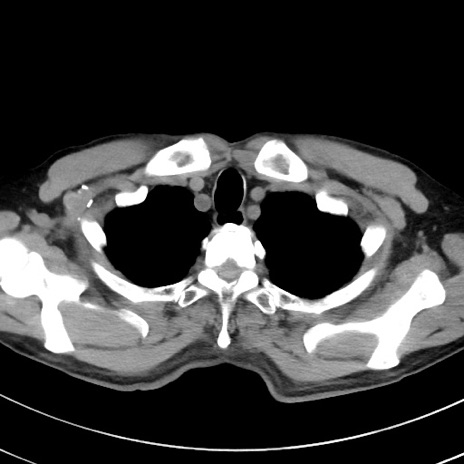

症例38(横断像)

【症例】70歳代 男性

【主訴】腹痛・嘔吐

【現病歴】昨晩より、嘔吐・腹痛あり。今朝になっても嘔吐あり。来院。

【既往歴】心臓バイパス手術、開腹胆摘、腸閉塞

【身体所見】BP 107/71mmHg、HR 116/min、腹部:平坦、軟、下腹部に軽度圧痛あり。反跳痛なし。

【データ】WBC 15100、CRP 0.32